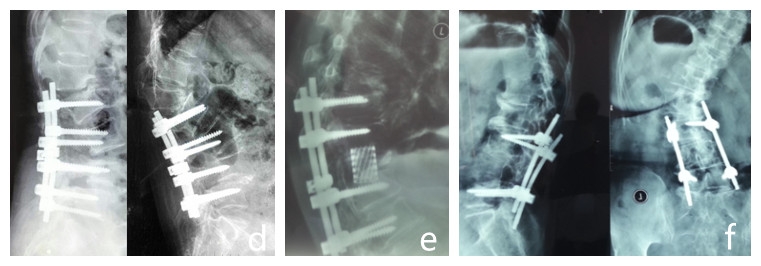

图5 脊柱远端融合节段越多,如包括L5-S1水平固定到骶骨或髂骨,发生交界性后凸的可能性越大

图6 长节段融合固定上固定椎(UIV)选择在胸10-12胸腰椎交界区是PJK的风险因素之一

图7 术前-术后1个月-术后1个月外观